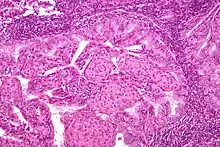

Pathology

- Epithelial tumors. For mesenchymal tumors, please see the uterine sarcomas page

- Endometrioid carcinoma (83%) - grouped based on degree of differentiation

- Adenocarcinoma

- Adenoacanthoma (adenocarcinoma with benign squamous metaplasia) - graded according to glandular component

- Adenosquamous carcinoma (mixed adenocarcinoma and squamous cell carcinoma) (81%)

- Type II

- Papillary serous adenocarcinoma (53%)

- Clear cell adenocarcinoma (63%)

- Most are well-differentiated, with proliferation of endometrial glands without intervening stroma

- Endometrial hyperplasia is thought to be a precursor lesion developed with unopposed estrogen and genetic events

- Simple vs complex hyperplasia based on glandular architecture

- Cytologic atypia increases risk of progression to carcinoma (complex atypical hyperplasia risk ~30%)

- Cells show microsatellite instability, PTEN, and k-ras mutations

- Papillary serous (1-5%)

- Complex papillary architecture, similar to papillary serous CA of ovary

- Presence of psammoma bodies

- Marked nuclear atypia

- Believed to transform from endometrial surface epithelium